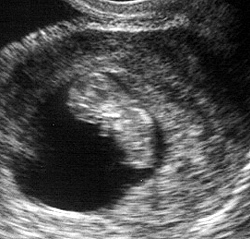

ينمو الجنين في هذا الأسبوع بشكل أكبر ويصبح حجمه في حجم حبة الفول ويصبح طوله 1.25 سم. يبدو شكل وحجم الرأس أكبر عن باقي حجم الجسم بشكل نسبي. ويستمر نمو الشكل الخارجي لتكوين أجزاء الوجه مع وجود بقع سوداء مكان العين وفتحتين صغيرتين جداً مكان الأنف وفتحة صغيرة جداً مكان الأذن. تبدأ براعم الأطراف في الظهور بشكل أوضح. تظهر اليدين والقدمين بشكل دائم الحركة وكأنها بدالات صغيرة.

تبدأ أيضاً الغدة النخامية وألياف العضلات في النمو في هذا الأسبوع. يبدأ القلب في النبض بشكل بسيط قد يكون غير مسموع بالنسبة لك ولكنه ينبض حوالي 150 نبضة في الدقيقة، وهو ضعف معدل النبضات الطبيعية لدى الشخص البالغ. يبدأ الطفل في منتصف الأسبوع السابع في القيام بأول حركة له، لكن لن تشعري بهذه الحركات إلا في المرحلة الثانية من الحمل (من 3 – 6 شهور).